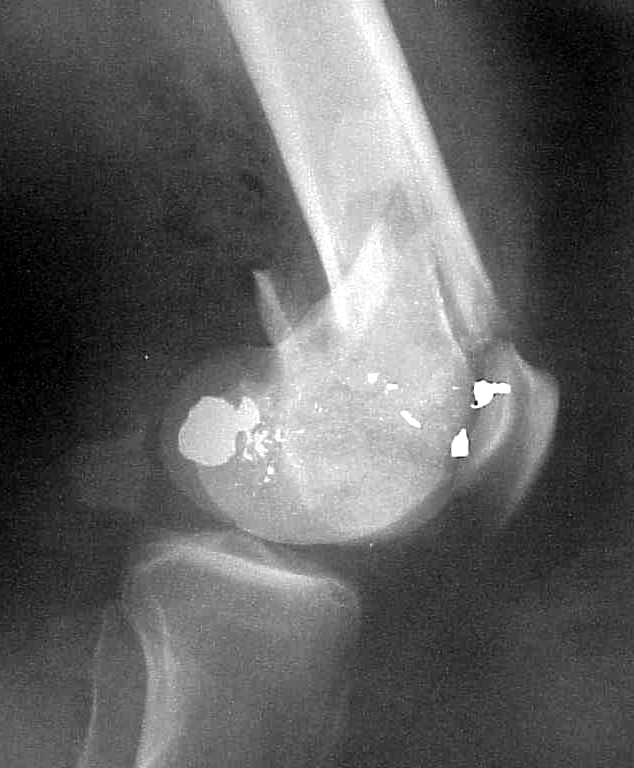

See attached case that was done several years ago before LISS. He had comminuted trochlea and anterior blocking screws were used to prevent anterior IMN cut-out.